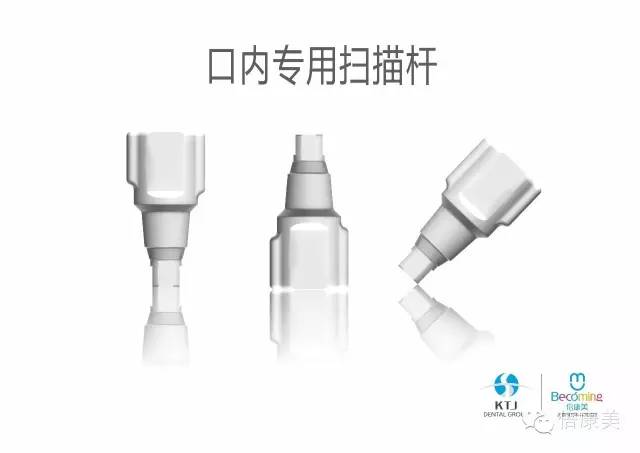

采用倍康美配套专用口内扫描杆,快速准确的获取口内种植数据